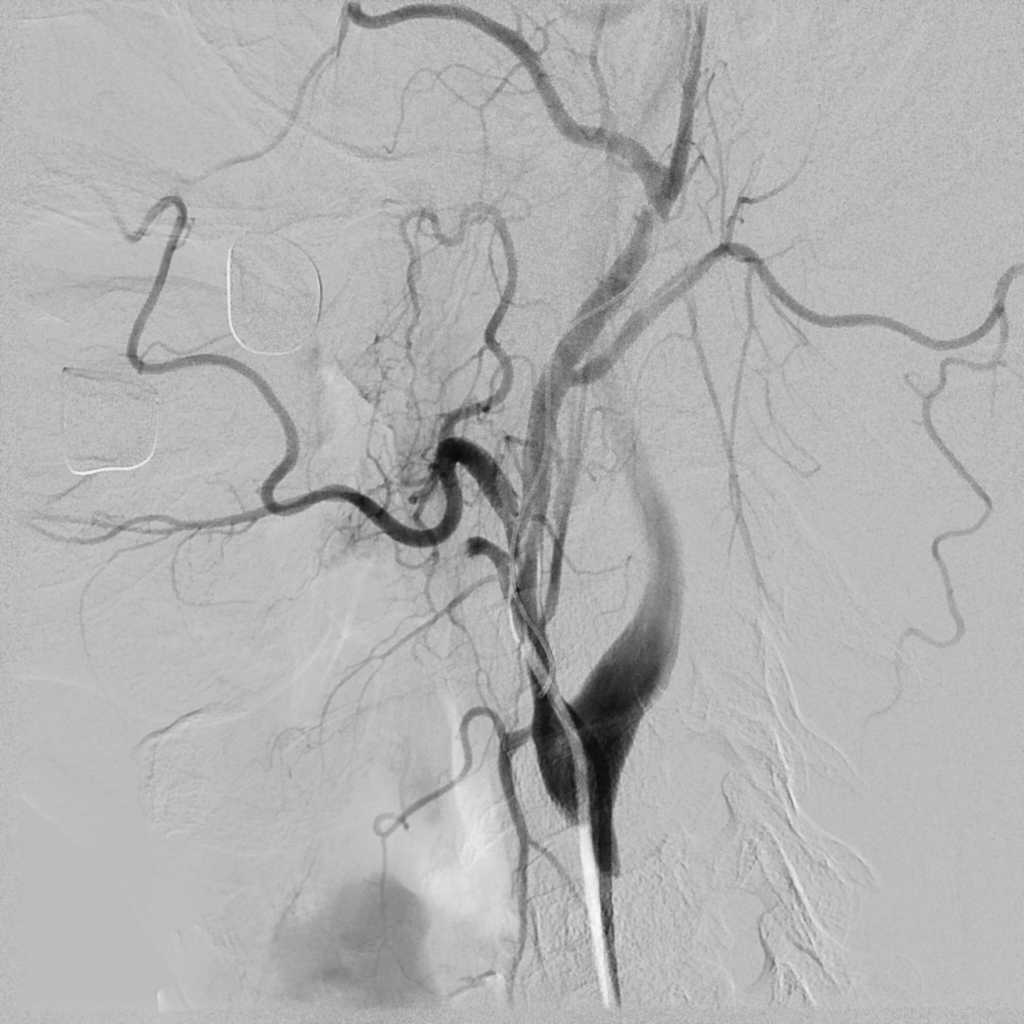

06.09.2011 был прооперирован пациент с опухолью языка с распадом, осложнившимся кровотечением. Внутрисосудисто, под местной анестезией пациенту была произведена селективная эмболизация язычной артерии и наружной сонной артерии. В послеоперационном периоде повторных эпизодов кровотечений не отмечено.

Селективная эмболизация артерий при опухолевых процессах позволяет предотвратить эпизоды кровотечений и уменьшить кровопотерю во время операций.